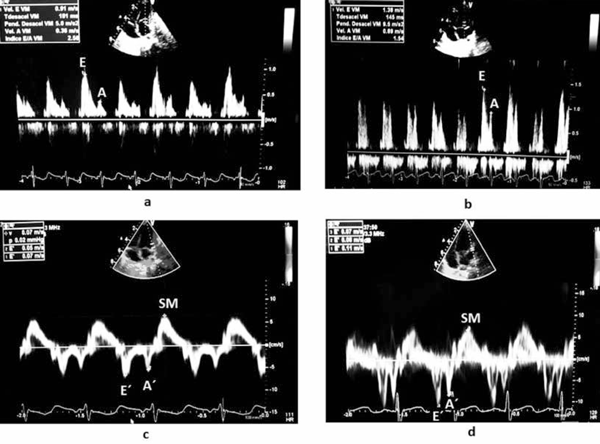

En el Doppler pulsado transmitral fue posible objetivar una relación E/A alterada de 2,5 a los 10 días del posoperatorio (onda A menor a percentil 10), que desciende a 0,9 a los 60 días. El Doppler tisular del anillo mitral evidenció función sistólica conservada con compromiso del llenado ventricular y posterior mejoría a los 60 días (incremento onda E´ y A´) (Figura 3). Es relevante destacar que la relación E/E´ varió poco en el período observado, de 14,3 a los 10 días a 13 a los 60 días (dentro de rango de referencia)7. Todo ello orienta a pensar en un mayor compromiso en la función auricular respecto a la función diastólica del VI. En el flujo Doppler de venas pulmonares se objetivó un patrón patológico a los 10 días con flujo retrógrado de onda S2 (sístole ventricular), bajo flujo anterógrado en onda D y flujo retrógrado de onda A. Podríamos atribuir este patrón a la rigidez de la aurícula asociada a una disfunción diastólica del VI, sin poder descartar influencia de la persistencia de shunt residual en dicho patrón (Figura 4). En el control a los 60 días presentó onda S unimodal con onda D predominante y pequeña onda A retrógrada, este patrón es el esperado en el posoperatorio alejado de esta patología8.

Figura 3: Registro Doppler transmitral en el caso 2 a los 10 (a) y 60 días (b) de la cirugía. Registro Doppler tisular anillo mitral caso 2 a los 10 (c) y 60 días (d) de la cirugía.